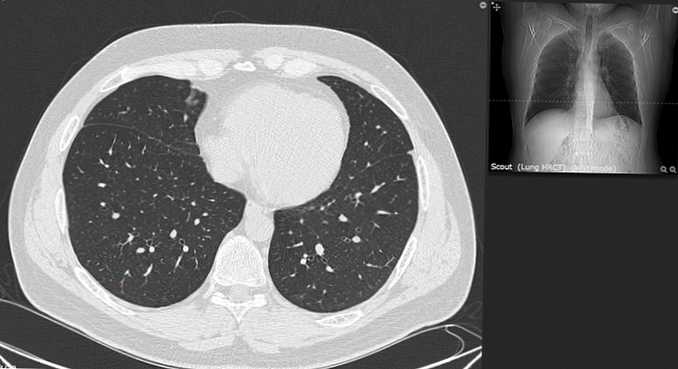

Рентгеновские и МРТ снимки легких